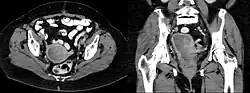

Das Leiomyosarkom (altgriechisch λεῖος leîos, ‚glatt, sanft‘ und μῦς mŷs, ‚Muskel‘, σάρκωμα, sárkoma, zu σάρξ sárx, „Fleisch“, „Weichteile“ und -om „Geschwulst“) ist ein bösartiger (maligner) Tumor, der von der glatten Muskulatur ausgeht. Er macht unter anderem etwa 1 % aller bösartigen Gebärmuttergeschwülste aus. Dieser Tumor tritt meist nach dem 30. Lebensjahr auf und hat seinen Altersgipfel in der 6. Lebensdekade. Die Symptome sind meist unspezifisch, es kommt bei Lokalisation in der Gebärmutter zu einer raschen Gebärmuttervergrößerung mit Blutungen. Leiomyosarkome können auch von der glatten Muskulatur an jeder anderen Stelle, z. B. auch von den Haarbalgmuskeln, ausgehen und somit prinzipiell an der gesamten Körperoberfläche auftreten.[1]

Diagnose

Aufgrund der unspezifischen Symptome ist die Diagnose meist ein Zufallsbefund, wenn aus anderen Gründen eine Operation notwendig war.

Das Leiomyosarkom ist im Operationspräparat normalerweise nicht vom Leiomyom zu unterscheiden, gegebenenfalls auftretende Nekrosen können einen Hinweis auf die Dignität liefern. Weiterhin sind Infiltrationen in das umliegende Gewebe wie z. B. bei Lokalisation in der Gebärmutter in das Myometrium, Endometrium oder Parametrium malignomverdächtig.